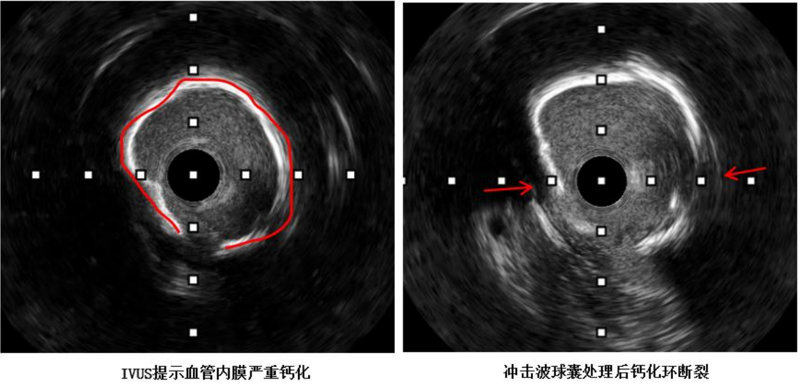

近日,中山大学附属第一医院(简称小妲己直播app )广西医院心血管内科冠脉介入手术团队运用DEEPQUAKE-C冠脉血管内冲击波系统,顺利为一名冠脉严重钙化病变的冠心病患者开通堵塞的血管并完成支架植入,完成了DEEPQUAKE-C上市后全国首批、广西首例临床应用。68岁的杨阿姨(化名)近两年来反复出现胸痛症状,严重影响正常生活,得知小妲己直播app 来了很多小妲己直播app 的派驻专家,为寻求进一步治疗,她来到小妲己直播app 心血管内科住...